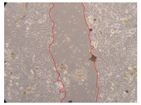

In the present study, the healing potential of 8 decoctions used in the preparation of ayahuasca was evaluated, using the wound scratch test. The evolution of the scratch created was monitored using microscopic images (Table 2) and the distance between the margins of the lesion was calculated (Table 3). Analysing the images that showed the evolution of the distance between the margins of the lesion and comparing them with the control samples, it was possible to verify that, in general, all the samples showed a great decrease in the lesion, and after 24 h of incubation, the samples of M. hostilis + P. harmala at 500 mg/L and P. viridis + B. caapi at 250 mg/L showed the best results. However, analysing the evolution of the distance calculated, only the sample of the commercial mixture at 250 mg/L after 2 h of incubation did not show a significant decrease. All other samples at different evaluation times, as well as the commercial mixture at 250 mg/L at the other times (8 h, 12 h and 24 h) showed a significant decrease in lesion margins compared to the control.

Table 2.

Microscopic images obtained from the scratch wound-healing assay with the samples of ayahuasca (magnification: 100×). The margins of the scratch appear in red.

These results are indicative of the healing activity of the samples tested. It is possible to observe in the images of Table 2 the migration of the fibroblasts incubated with the samples at different concentrations. In these images, it was possible to verify that the lesions closed over time, which was in accordance with the distance calculated between the margins of the lesion. As far as we know, to date there are no studies where the healing potential of ayahuasca has been evaluated, and it is not possible to compare the results now obtained. However, these results can be explained by the antioxidant and anti-inflammatory activity previously studied in these samples [], since it is reported that antioxidant activity and healing properties coexist in plant extracts []. Wound healing consists of the reconstruction of the lesion, involving several interactions between epithelial cells, growth factors, cytokines and chemokines. It has been reported that natural products, namely plant extracts, are involved in the proliferation of fibroblasts and keratinocytes, and may contain cell adhesion molecules, growth factors and cell signalling molecules, which can promote lesion reconstruction []. This in vitro assay, which, unlike conventional assays used to determine the healing properties of plant material, was non-invasive, allowed the screening of several samples with antibacterial, anti-inflammatory and antioxidant properties, which are important in wound healing [,].